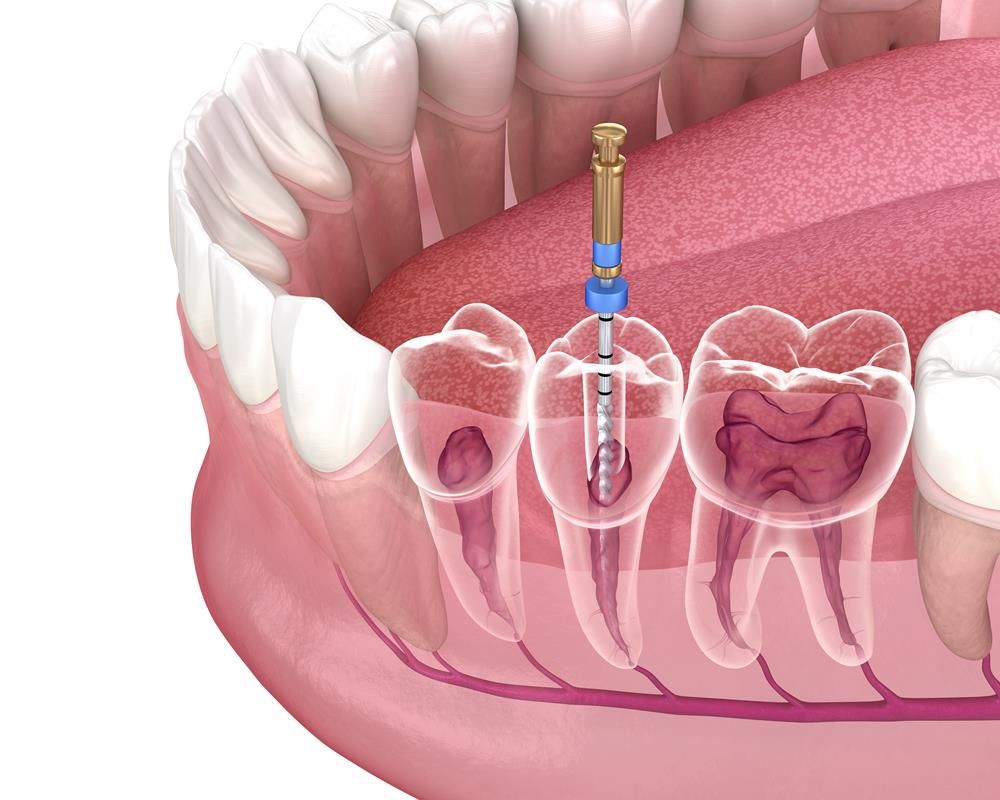

Root Canal Treatment

Can be completed in a single visit